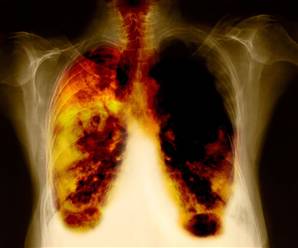

2. Lung Cancer

When uncontrolled cell growth is seen in the tissues of the lungs, Lung cancer is said to develop. This growth can lead to metastasis, which is the infiltration or invasion of adjacent tissue. Carcinomas of the lung are the majority of primary lung cancers. Lung cancer is the most common cause of cancer-related death in men and the second most common in women.